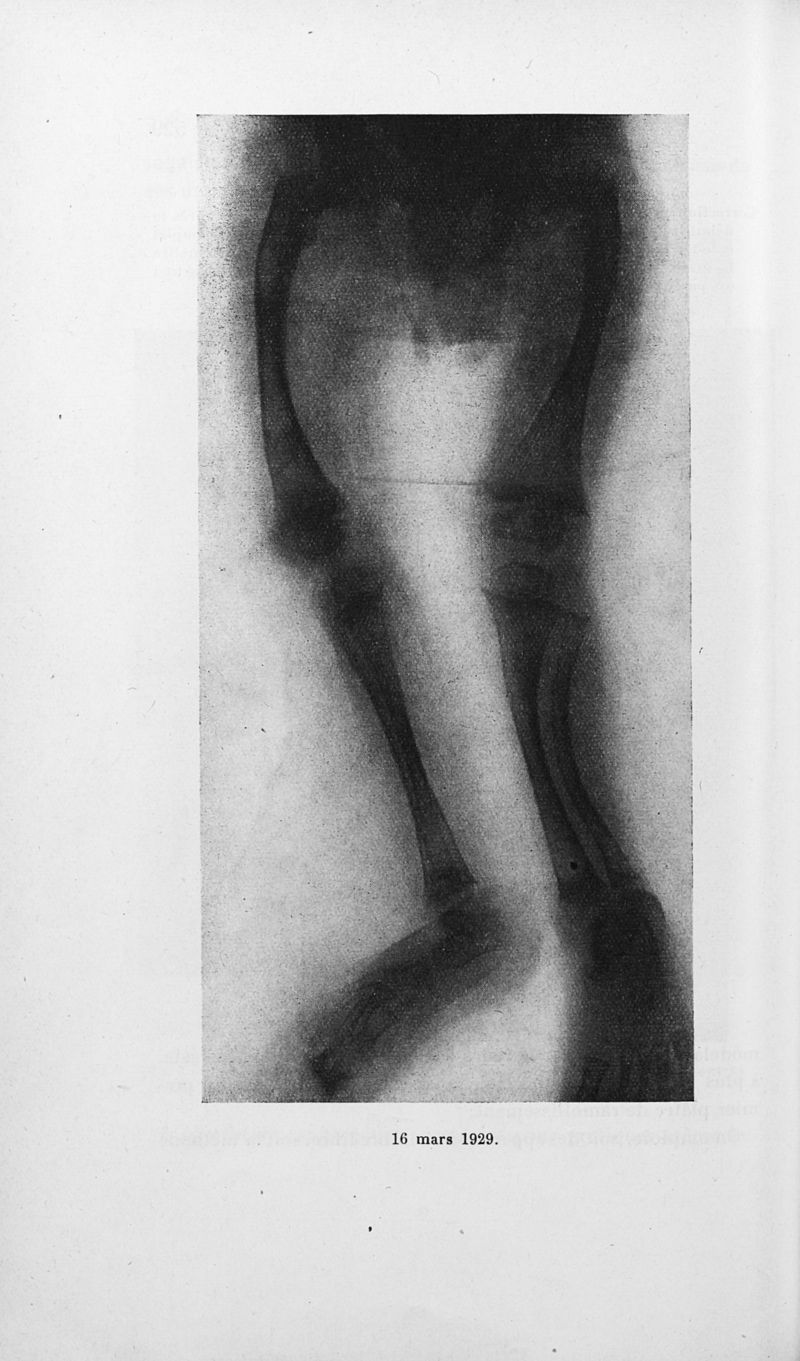

Bulletins de la société de pédiatrie de Paris

Tome trentième. - Paris : Masson et Cie, 1932.